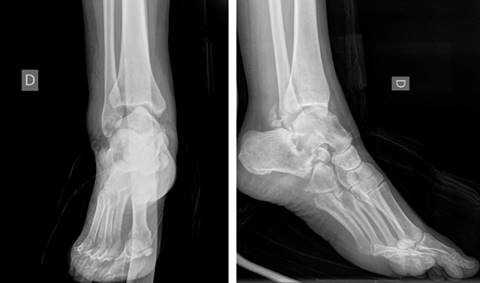

Las radiografías de tobillo y pie mostraron una subluxación tibioastragalina junto a una luxación subastragalina lateral (Figura 2). Se decidió completar el estudio con una TAC (Figura 3), que demostró una fractura del sustentaculum tali y un arrancamiento en el canto posterior del maléolo peroneo (fleck sign) sugestiva de afectación del canal retromaleolar (Figura 4).

Con respecto a las pruebas de imagen, en la radiografía simple en proyecciones anteroposterior y perfil, la presencia de una subluxación de astrágalo en la mortaja tibioperonea (presente en nuestro caso) en el contexto de una caída de altura nos debe poner en alerta ante la posibilidad de que exista una luxación lateral subastragalina.7